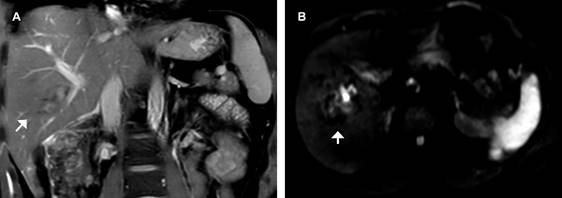

La resonancia magnética en secuencias simples confirmó hematomas intraparenquimatosos (Figura 1). Las secuencias contrastadas en fases tempranas muestran integridad de la vena porta, arteria hepática y venas suprahepáticas (Figura 2A). En fase hepatobiliar se demuestran tres laceraciones hepáticas cercanas al hilio en segmentos V y VI en grado II de la American Association for the Surgery of Trauma (AAST) (Tabla 1). Los conductos biliares derecho anterior y posterior e izquierdo son demostrados como imágenes tubulares sin evidencia de fuga (Figura 2B y C).

Figura 1: Coronal T2 FS. A) Hematoma en segmento V asociado a la rama derecha posterior de la porta (flecha). B) Restricción focal a la difusión cercano al hilio en secuencia de difusión B 1,000 ms, confirma el hematoma.